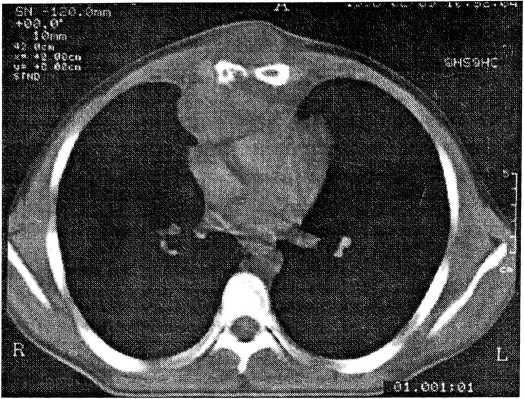

При КТ в легких очаговых теней не обнаружено. Начиная с уровня бифуркации трахеи выявляется объемное многоузловое образование размером 9 × 7,5 × 6,6 см неоднородной структуры плотностью +50 ед., инфильтрирующее грудину (деструкция нижней трети тела на уровне VIII грудного позвонка). Частично разрушены нижняя треть грудины, прилежащие реберные хрящи, инфильтрированы подкожная клетчатка и переднее средостение (рис. 1). Образование интимно прилежит к передним отделам сердца и, скорее всего, прорастает перикард. Клетчатка верхнего отдела средостения неравномерно уплотнена, на этом фоне определяются увеличенные лимфатические узлы. Заключение: злокачественная опухоль грудной стенки, прорастающая в переднее средостение и перикард.

Рис. 1. Компьютерная томограмма. Объемное образование размером 9 × 7,5 × 6,6 см с неоднородной структурой, плотностью +50 ед., инфильтрирующее грудину (деструкция нижней трети ее тела на уровне VIII грудного позвонка). Опухоль прорастает подкожную клетчатку и переднее средостение, интимно прилежит к передним отделам сердца.